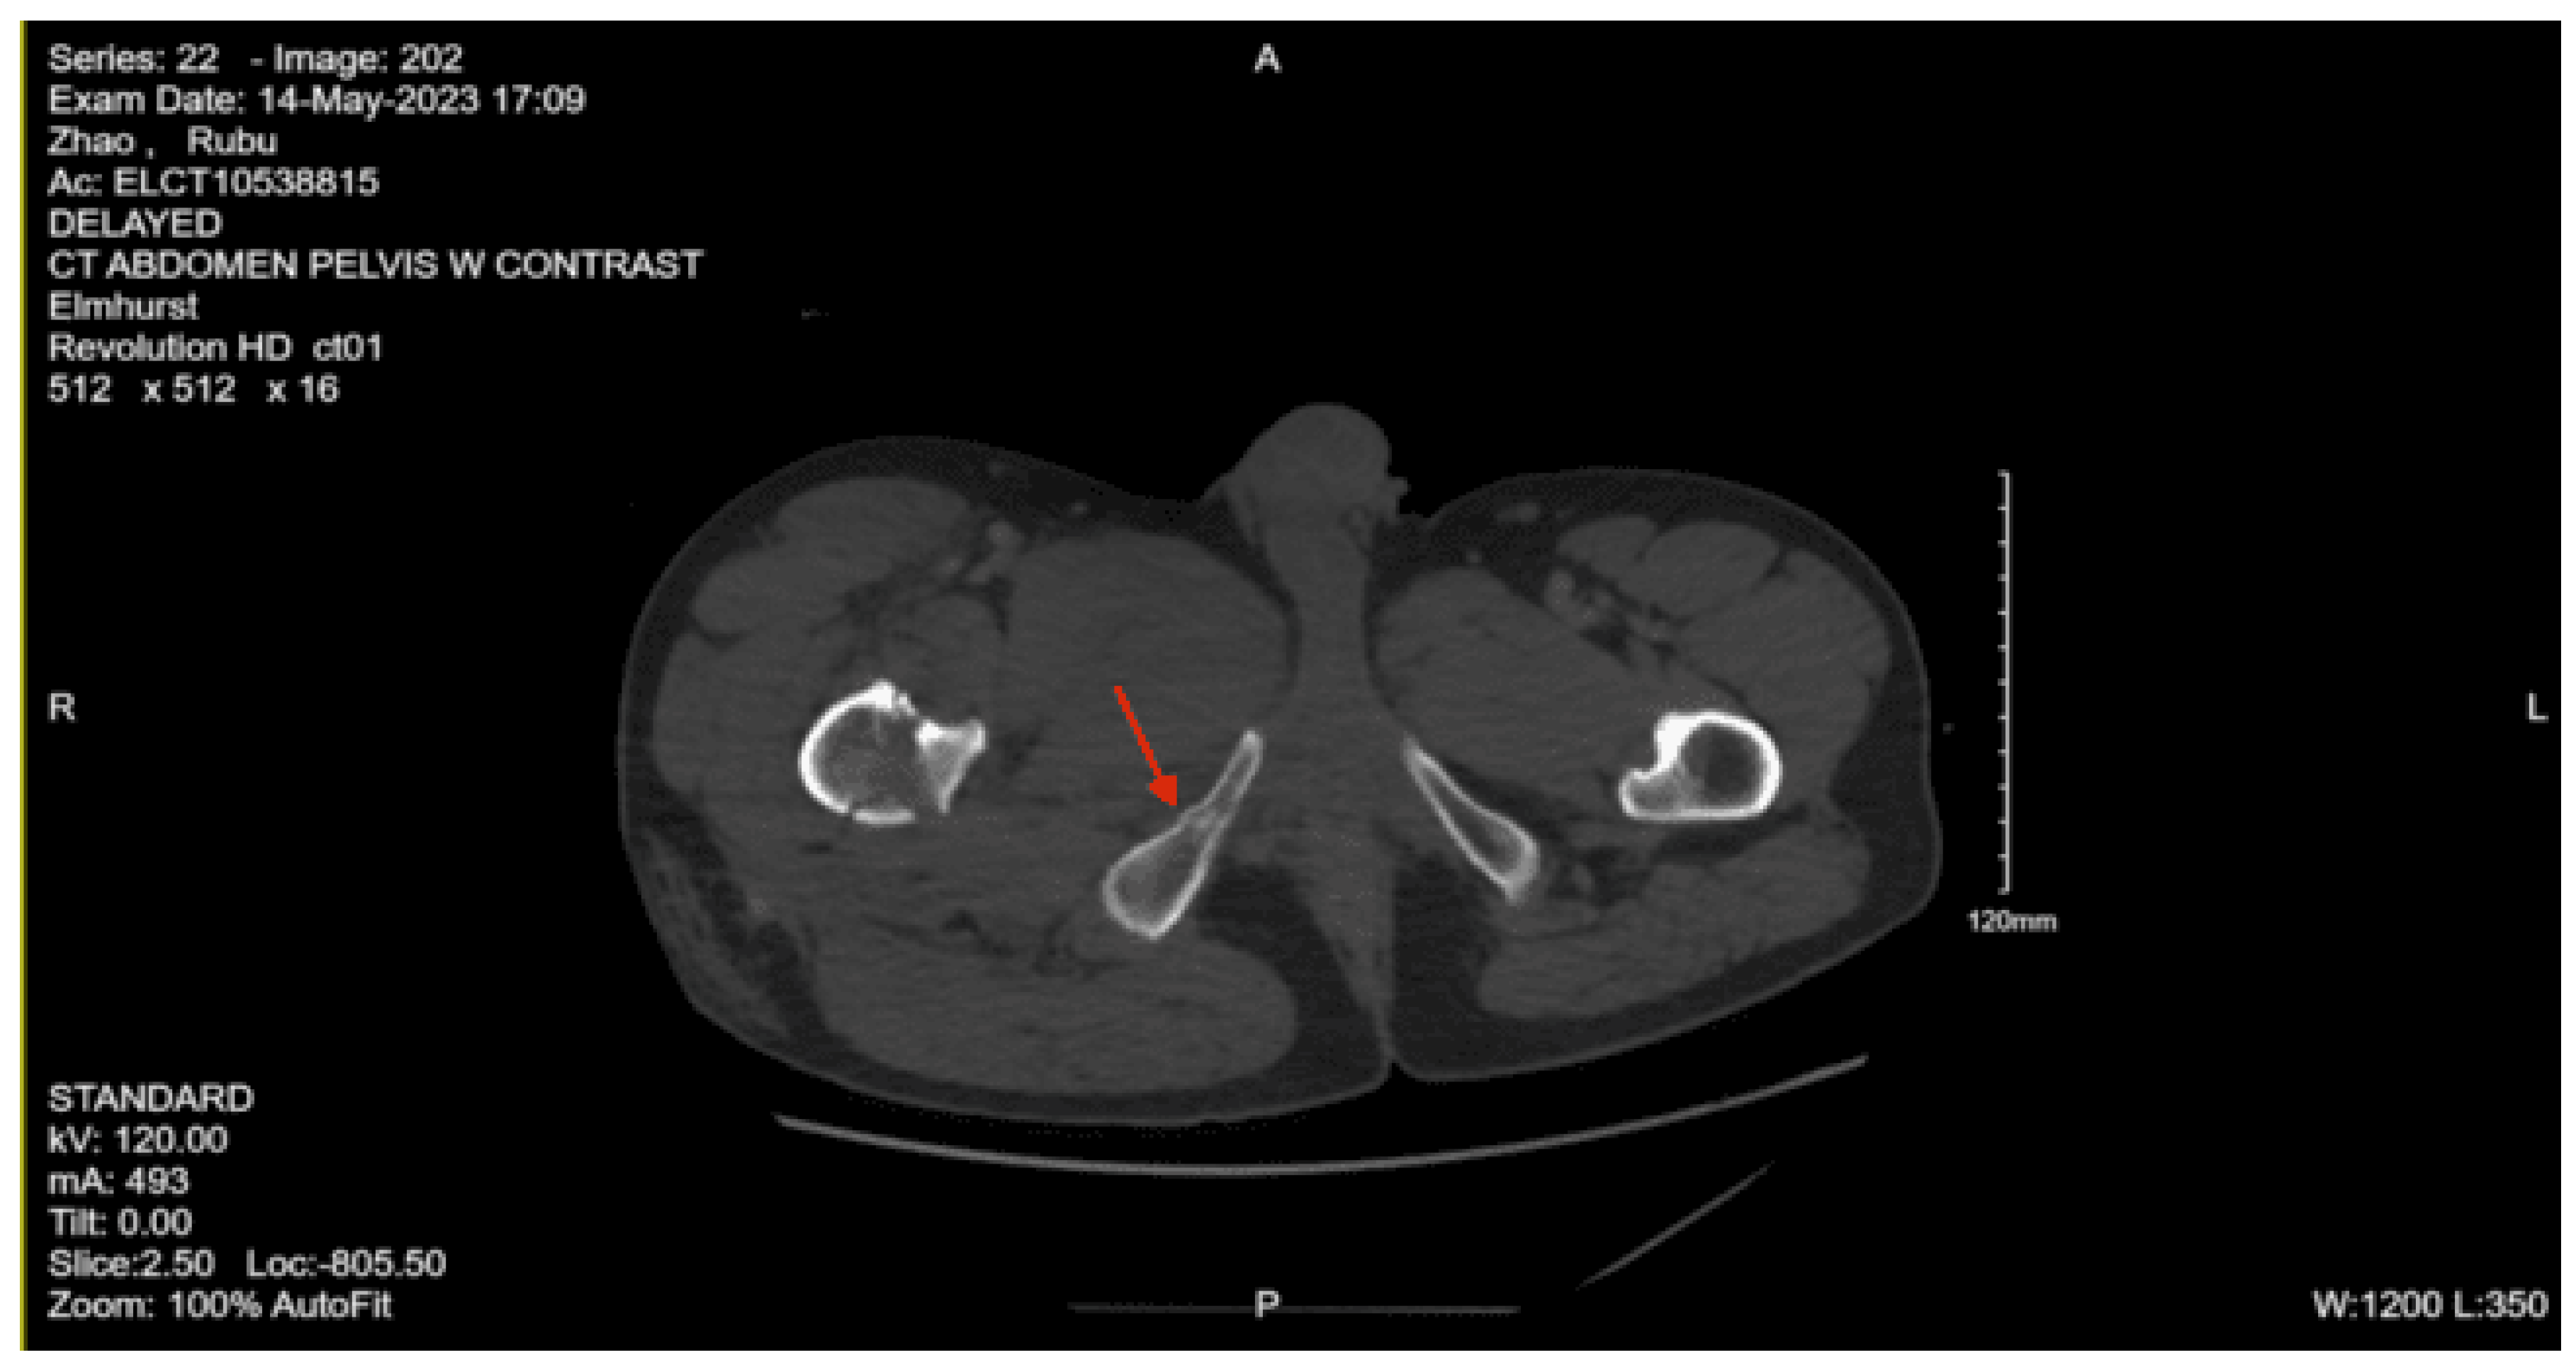

Imaging as shown in Figure 19 and Figure 20:

CT Abdomen Pelvic with contrast: No evidence of acute visceral injury. Redemonstration of fractures of the proximal right femur. Fractures of the right inferior petrous and right transverse processes of L2 and L3.

CT femur w/o contrast, Right: Comminuted fracture of the proximal subtrochanteric right femur with posterior medial displacement. Nondisplaced fracture of the right inferior pubic ramus.